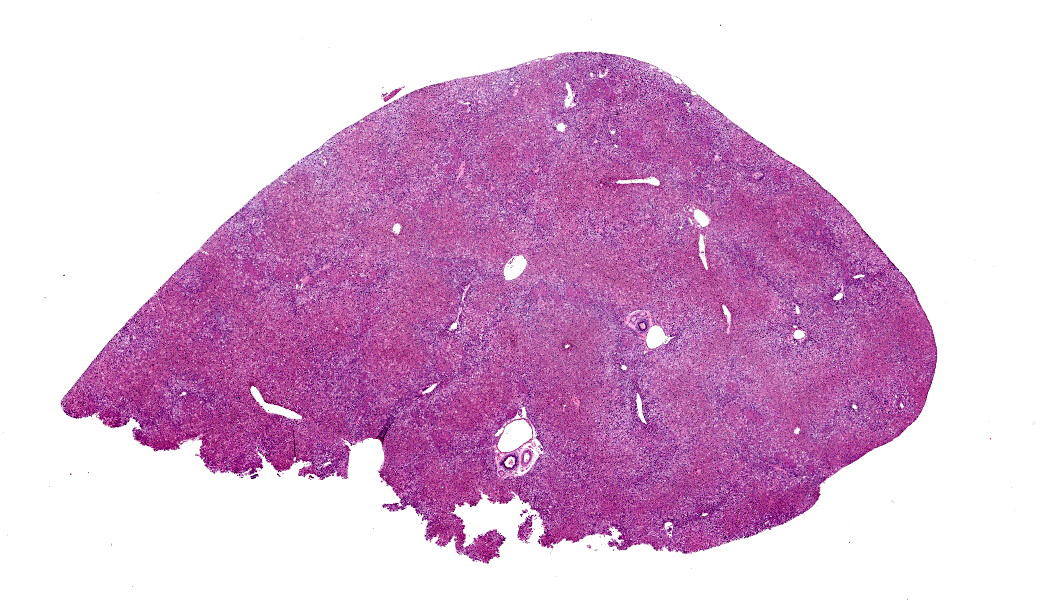

Microscopic Description: Approximately 60% of the hepatocytes in mostly periportal and centrilobular regions are markedly expanded by high numbers of microvesicular vacuolations (steatosis/lipid) and more rarely macrovesicular vacuolations or a mixture of the two. Sinusoids contain increased myofibroblasts (activated hepatic stellate cells) causing multifocal collapse of hepatocellular cord architecture. The myofibroblasts extend near portal areas, but distinct biliary hyperplasia is not appreciated. Occasionally hepatocytes are dissociated and composed of hypereosinophilic cytoplasm and lack a nucleus (necrosis). There are occasional binucleated hepatocytes. Canaliculi are multifocally, mildly expanded by tan to brown material (bile). Very rare lymphocytes are within sinusoids and in portal areas.

Contributor’s Morphologic Diagnoses: Severe, chronic, multifocal to coalescing microvesicular and macrovesicular steatosis with sinusoidal fibrosis and cholestasis

JPC Diagnoses: Liver: Hepatocellular micro- and macrovesicular lipidosis, chronic, multifocal to coalescing, severe, with marked stellate cell hyperplasia and cholestasis.